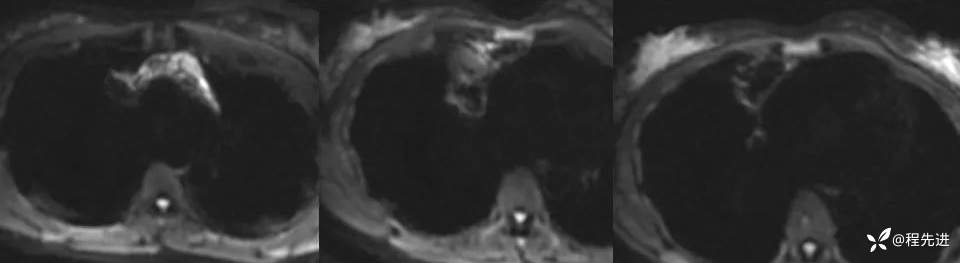

增强